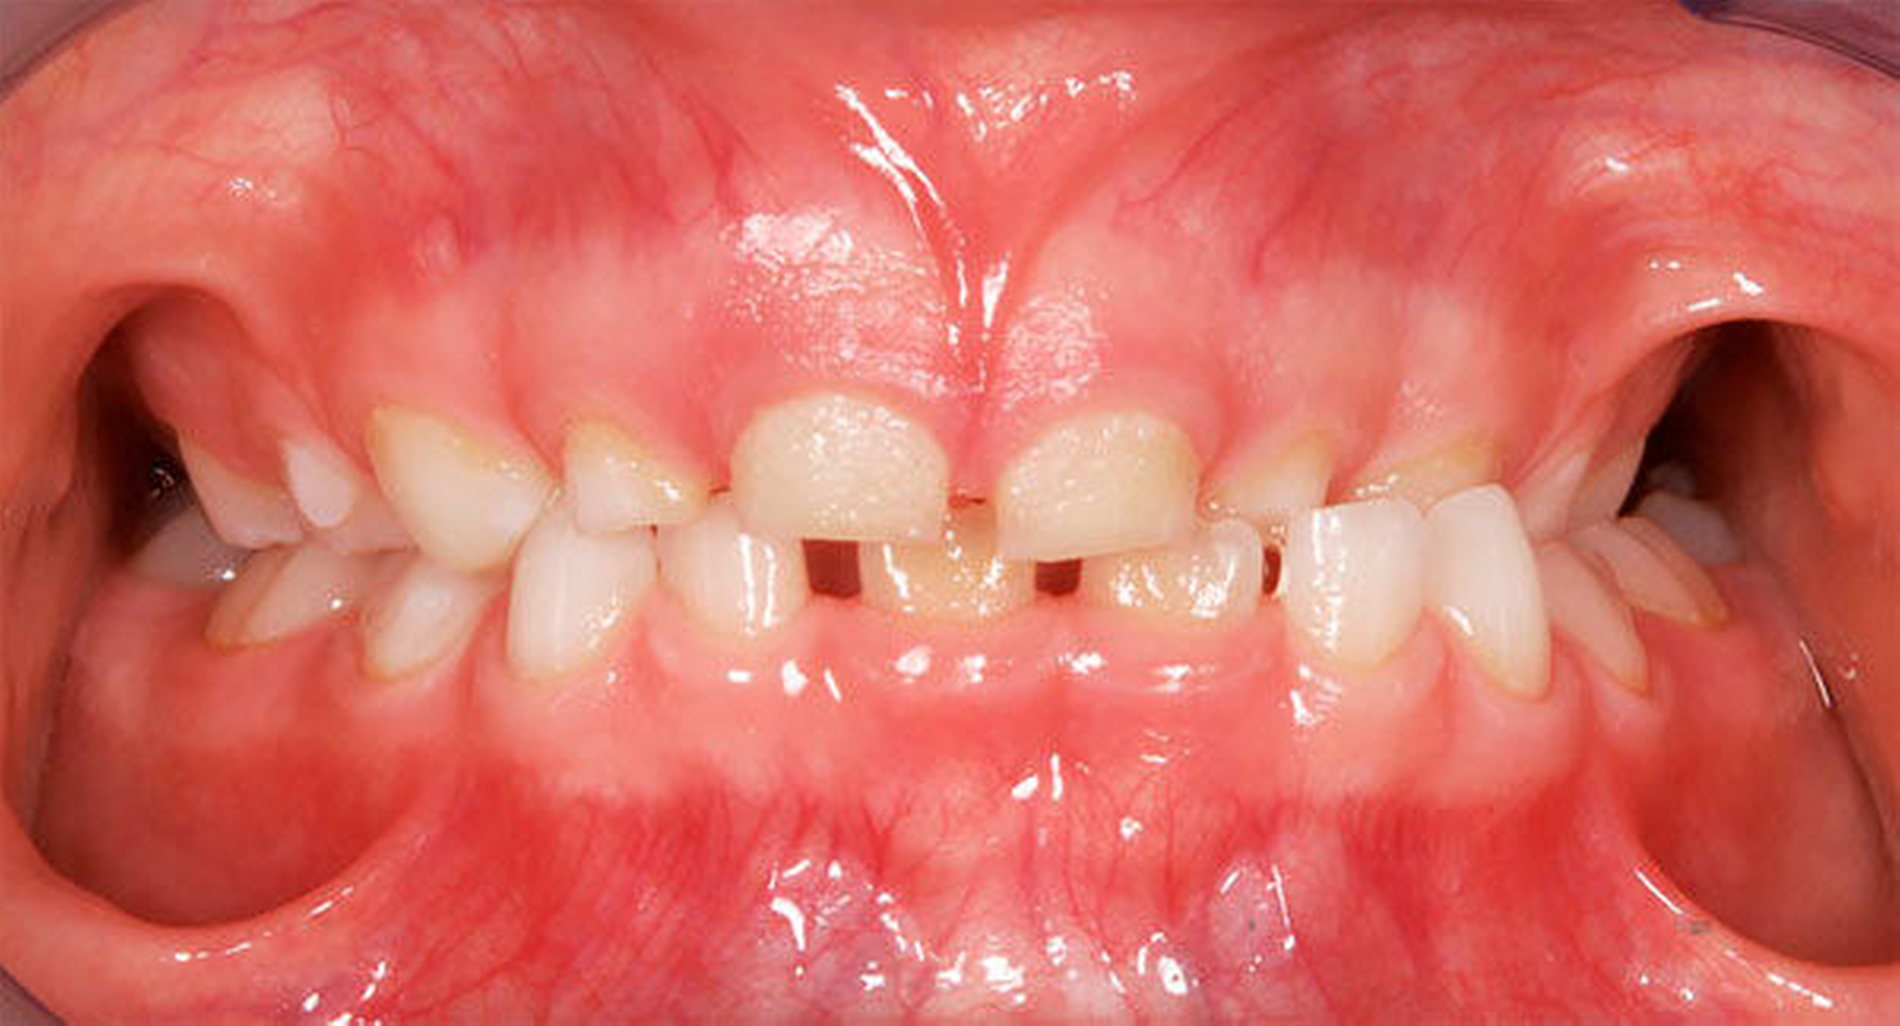

Ausgeprägte Zahnfehlstellungen und Gebissanomalien zeigen sich im reinen Milchgebiss deutlich seltener als im Wechsel- oder im permanenten Gebiss [Schopf, 2003]. Dennoch sollten bereits in dieser frühen Phase beispielsweise die Platzverhältnisse für die später durchbrechenden Zähne beurteilt werden. Im Säuglingskiefer liegen die Zahnkeime der Milch-Inzisiven zunächst in einer sagittalen Staffelstellung [van der Linden, 1980]. Die mit dem Durchbruch der Milchzähne einhergehende Bildung des Alveolarfortsatzes und die wachstumsbedingte Vergrößerung der Zahnbögen führt meist zu einer lückigen Stellung der Milchschneidezähne [Sillman, 1964] (Abbildung 1). Diese Lücken tragen dazu bei, den deutlich breiteren bleibenden Nachfolgern eine regelrechte Einordnung in den Zahnbogen zu ermöglichen [Moyers, 1976; Leighton, 1978]. Ein „schönes“, lückenloses Milchgebiss oder gar Engstände in der Front sind ein Alarmsignal im Hinblick auf spätere Platzprobleme für die bleibenden Zähne [Leighton, 1969]. Bei diesen Patienten ist eine intensive Überwachung während des Zahnwechsels der permanenten Inzisiven ratsam, um gegebenenfalls rechtzeitig Platz schaffende Maßnahmen einleiten zu können.